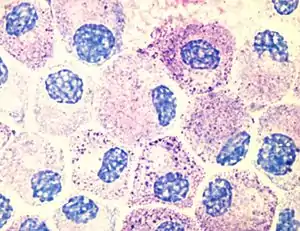

Морфологически тучные клетки очень близки к базофилам в кровотоке. И тучные клетки, и базофилы содержат базофильные гранулы с гепарином и гистамином. Однако между двумя типами клеток есть и различия в строении: так, у тучных клеток ядро округлое, а у базофилов разделено на доли. Округлое ядро мастоцитов находится центрально, часто замаскировано цитоплазматическими гранулами[5]. Тучные клетки и базофилы связываются с Fc-участками молекул иммуноглобулинов E (IgE), связавшими антиген (кросс-связывание), в результате чего запускается высвобождение содержимого гранул. Из-за сходства с базофилами тучные клетки иногда называют тканевыми базофилами. Кроме того, базофилы и тучные клетки происходят от одного и того же костномозгового предшественника, экспрессирующего CD34. Базофилы покидают костный мозг зрелыми, в то время как созревание тучных клеток завершается после их оседания в тканях. Место оседания тучных клеток может влиять на некоторые их свойства[6].

Тучные клетки присутствуют в большинстве тканей и, как правило, располагаются вблизи сосудов и нервов. Они особенно многочисленны в тканях, залегающих на границе организма с внешней или внутренней средой: коже, слизистой лёгких и пищеварительного тракта, а также в ротовой и носовой полостях и конъюнктиве[6]. В подслизистом слое слизистых, дерме, серозных оболочках, селезёнке и периваскулярной соединительной ткани тучные клетки содержатся в количестве 104—106 на 1 г ткани. На гистологических препаратах тучные клетки легко визуализируются при помощи окрашивания толуидиновым синим или алциановым синим[7]. Для тучных клеток характерен эффект метахромазии при окрашивании анилиновыми красителями из-за большого количества кислых радикалов протеогликанов[5].